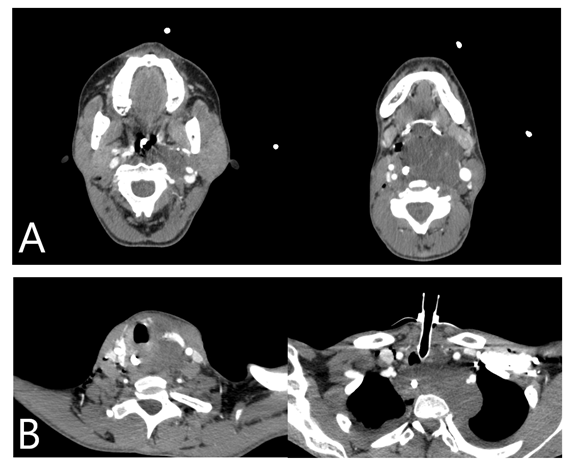

Figure 1 Axial CT findings: A and B Showed a hypoattenuating solid expansive lesion, affecting the left superior parapharyngeal space, carotid space, extends inferiorly to the hypopharynx and retropharyngeal space, obliterating the supraglottis and glottis.